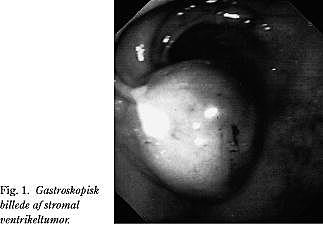

En 64-årig mand, som blev indlagt på medicinsk afdeling til udredning for anæmi (Hb 3,6 mmol/l). Patienten havde op til indlæggelsen været træt og haft sort afføring. Ingen symptomer i øvrigt. Han var i behandling med hjertemagnyl 75 mg dgl. på grund af tidligere AMI. En gastroskopi viste midt på forvæggen af ventriklen en ca. 3 cm i diameter, bredbaset polyplignende dannelse med et fibrinbelagt ulcus i midten (Fig. 1 ). Der blev biopteret herfra. Mikroskopi viste en gastrointestinal stromal tumor (GIST). Man kunne på det foreliggende grundlag ikke udtale sig om tumorens biologiske potentiale. EUL viste, at tumoren var submukøst beliggende (Fig. 2 ). Ventrikelvæggen i øvrigt var normal. CT af thorax og abdomen viste normale forhold. Der blev herefter foretaget laparoskopisk kileresektion af tumoren. Efter etablering af pneumoperitoneum med Veress kanyle indførtes 10 mm trokar samt 30 grader optik ved umbilicus. Der indførtes herefter en 12 mm trokar lateralt i højre hypochondrium og en 15 mm trokar lateralt i venstre hypochondrium. Ved hjælp af en laparoskopisk UL-scanner sikrede man sig tumorens beliggenhed. På begge sider af og lateralt for tumoren sattes i ventriklens forvæg en 2-0 Ethilon holdetråd dobbeltarmeret på lige nåle, som førtes gennem bugvæggen. Man kunne således holde op i det tumorbærende område af ventriklens forvæg, som herefter blev kileformet reseceret i UL-bedømt sundt væv med ENDO GIA II 60 4.8. SULU indført gennem 15 mm trokaren. Resektatet blev anbragt i en pose (LiNA Endobag: EB 60) og fjernet gennem trokarstedet i ve. hypochondrium. Operationstiden var 45 min. Patienten blev udskrevet tre dage efter operationen og kontrolleret første gang ambulant en måned herefter. Det postoperative forløb var helt ukompliceret. Mikroskopi af ventrikelresektatet viste GIST af borderline -type med frie resektionsrande.